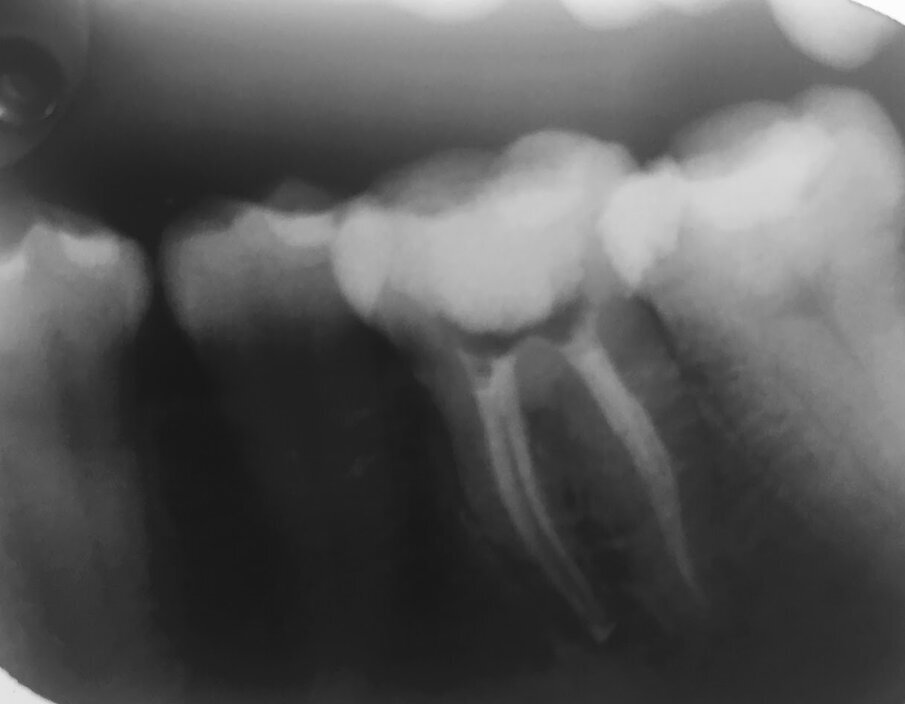

Dr Margaret Tui, a clinician based in the Philippines, agrees that the increased fatigue resistance and strong flexibility of both HyFlex systems allowed her to manage an S-shaped case more easily. At a recent COLTENE Train the Trainer event, she presented a mandibular first molar case with four canals that was referred to her by another dentist who could not negotiate the canal owing to its difficult anatomy. After utilising the crown-down technique and the HyFlex CM files to flare the coronal third of the distobuccal and distolingual canals, Tui then continued to use HyFlex EDM to negotiate the mesiobuccal and mesiolingual canals, as she had discovered a slight curvature in the middle third of the canals. As for the S-shaped distobuccal and distolingual canal, she continued with the Hyflex CM files. Post obturation radiograph showed properly shaped canals with proper healing.

Fig. 6: Dr Margaret Tiu presented a mandibular first molar case with four canals. She used a combination of HyFlex CM and HyFlex EDM to properly shape the canals.

Post obturation radiograph